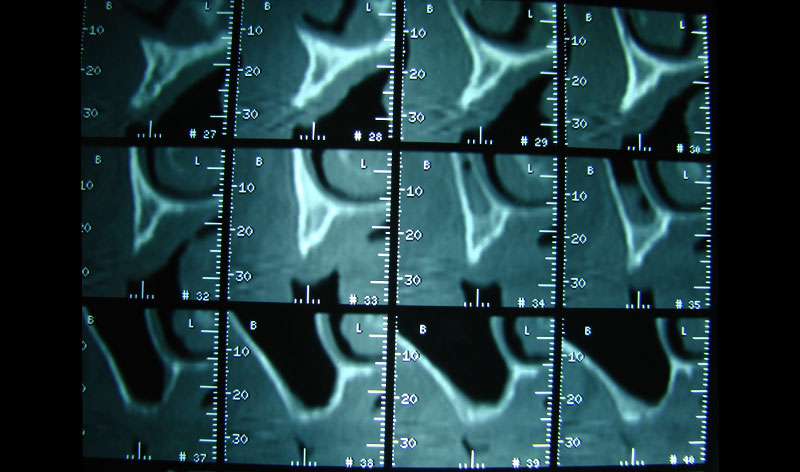

Existen muchas situaciones donde la pérdida y la atrofia ósea son tan graves que nos obligan a recurrir a la cresta iliaca del paciente, para conseguir el volumen óseo necesario para la correcta reconstrucción del maxilar. Así, la colocación de implantes será posible a los 3 meses.